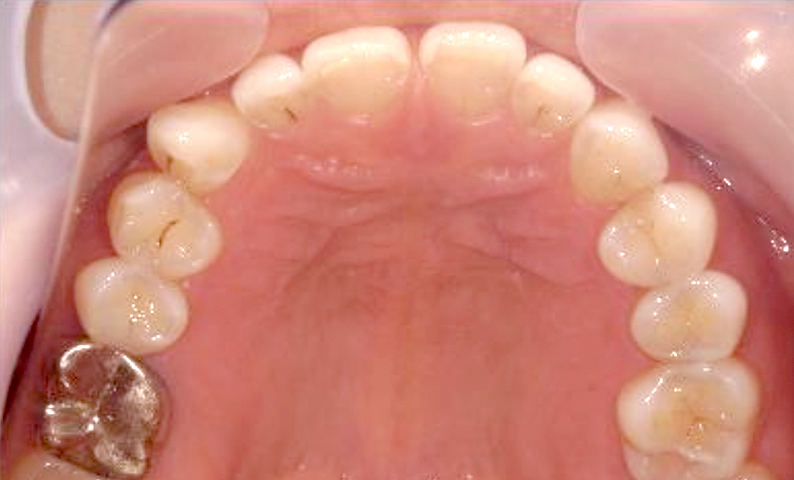

症例:上顎だけの部分矯正

治療期間:7ヶ月金額:24万円+税10代女性すきっ歯上の前歯だけ歯の形態修正

| Before | After |